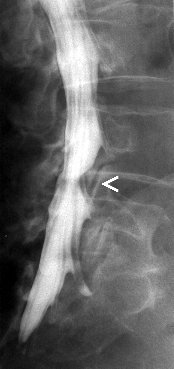

Myelografie is het in beeld brengen

van het ruggenmergkanaal door middel van een cotrasmiddel. Deze wordt

door middel van een punctie ingespoten in de duraal zak in de lage rug.

Er wordt dus in de rug geprikt zodat een naald door kan schuiven tussen

de wervels tot in het ruggenmergkanaal. Dit kan gebeuren onder

plaatselijke verdoving, maar dit is geen regel. Gesteld wordt dat er in

elk geval moet geprikt worden. Er kunnen opnames genomen worden ter

hoogte van de hals, borst of lage rug. Na de punctie worden er

conventionele opnames gemaakt waarna de patiënt naar de CT-scan

wordt gebracht om axiale beelden te maken in de regio waar zich

mogelijk problemen voordoen.

Het is echter zo dat deze onderzoek

steeds vaker vervangen wordt door een MRI vande rug, daar dit minder

invasief is, minder risicos inhoudt en beter verdragen wordt door de

patiënten.

Het opsporen van een degeneratieve tussenwervelschijf |

Tumoraal proces tussen de wervels |

Trama met fractuur of verplaatsing van een wervel |

Post opperatieve problemen |